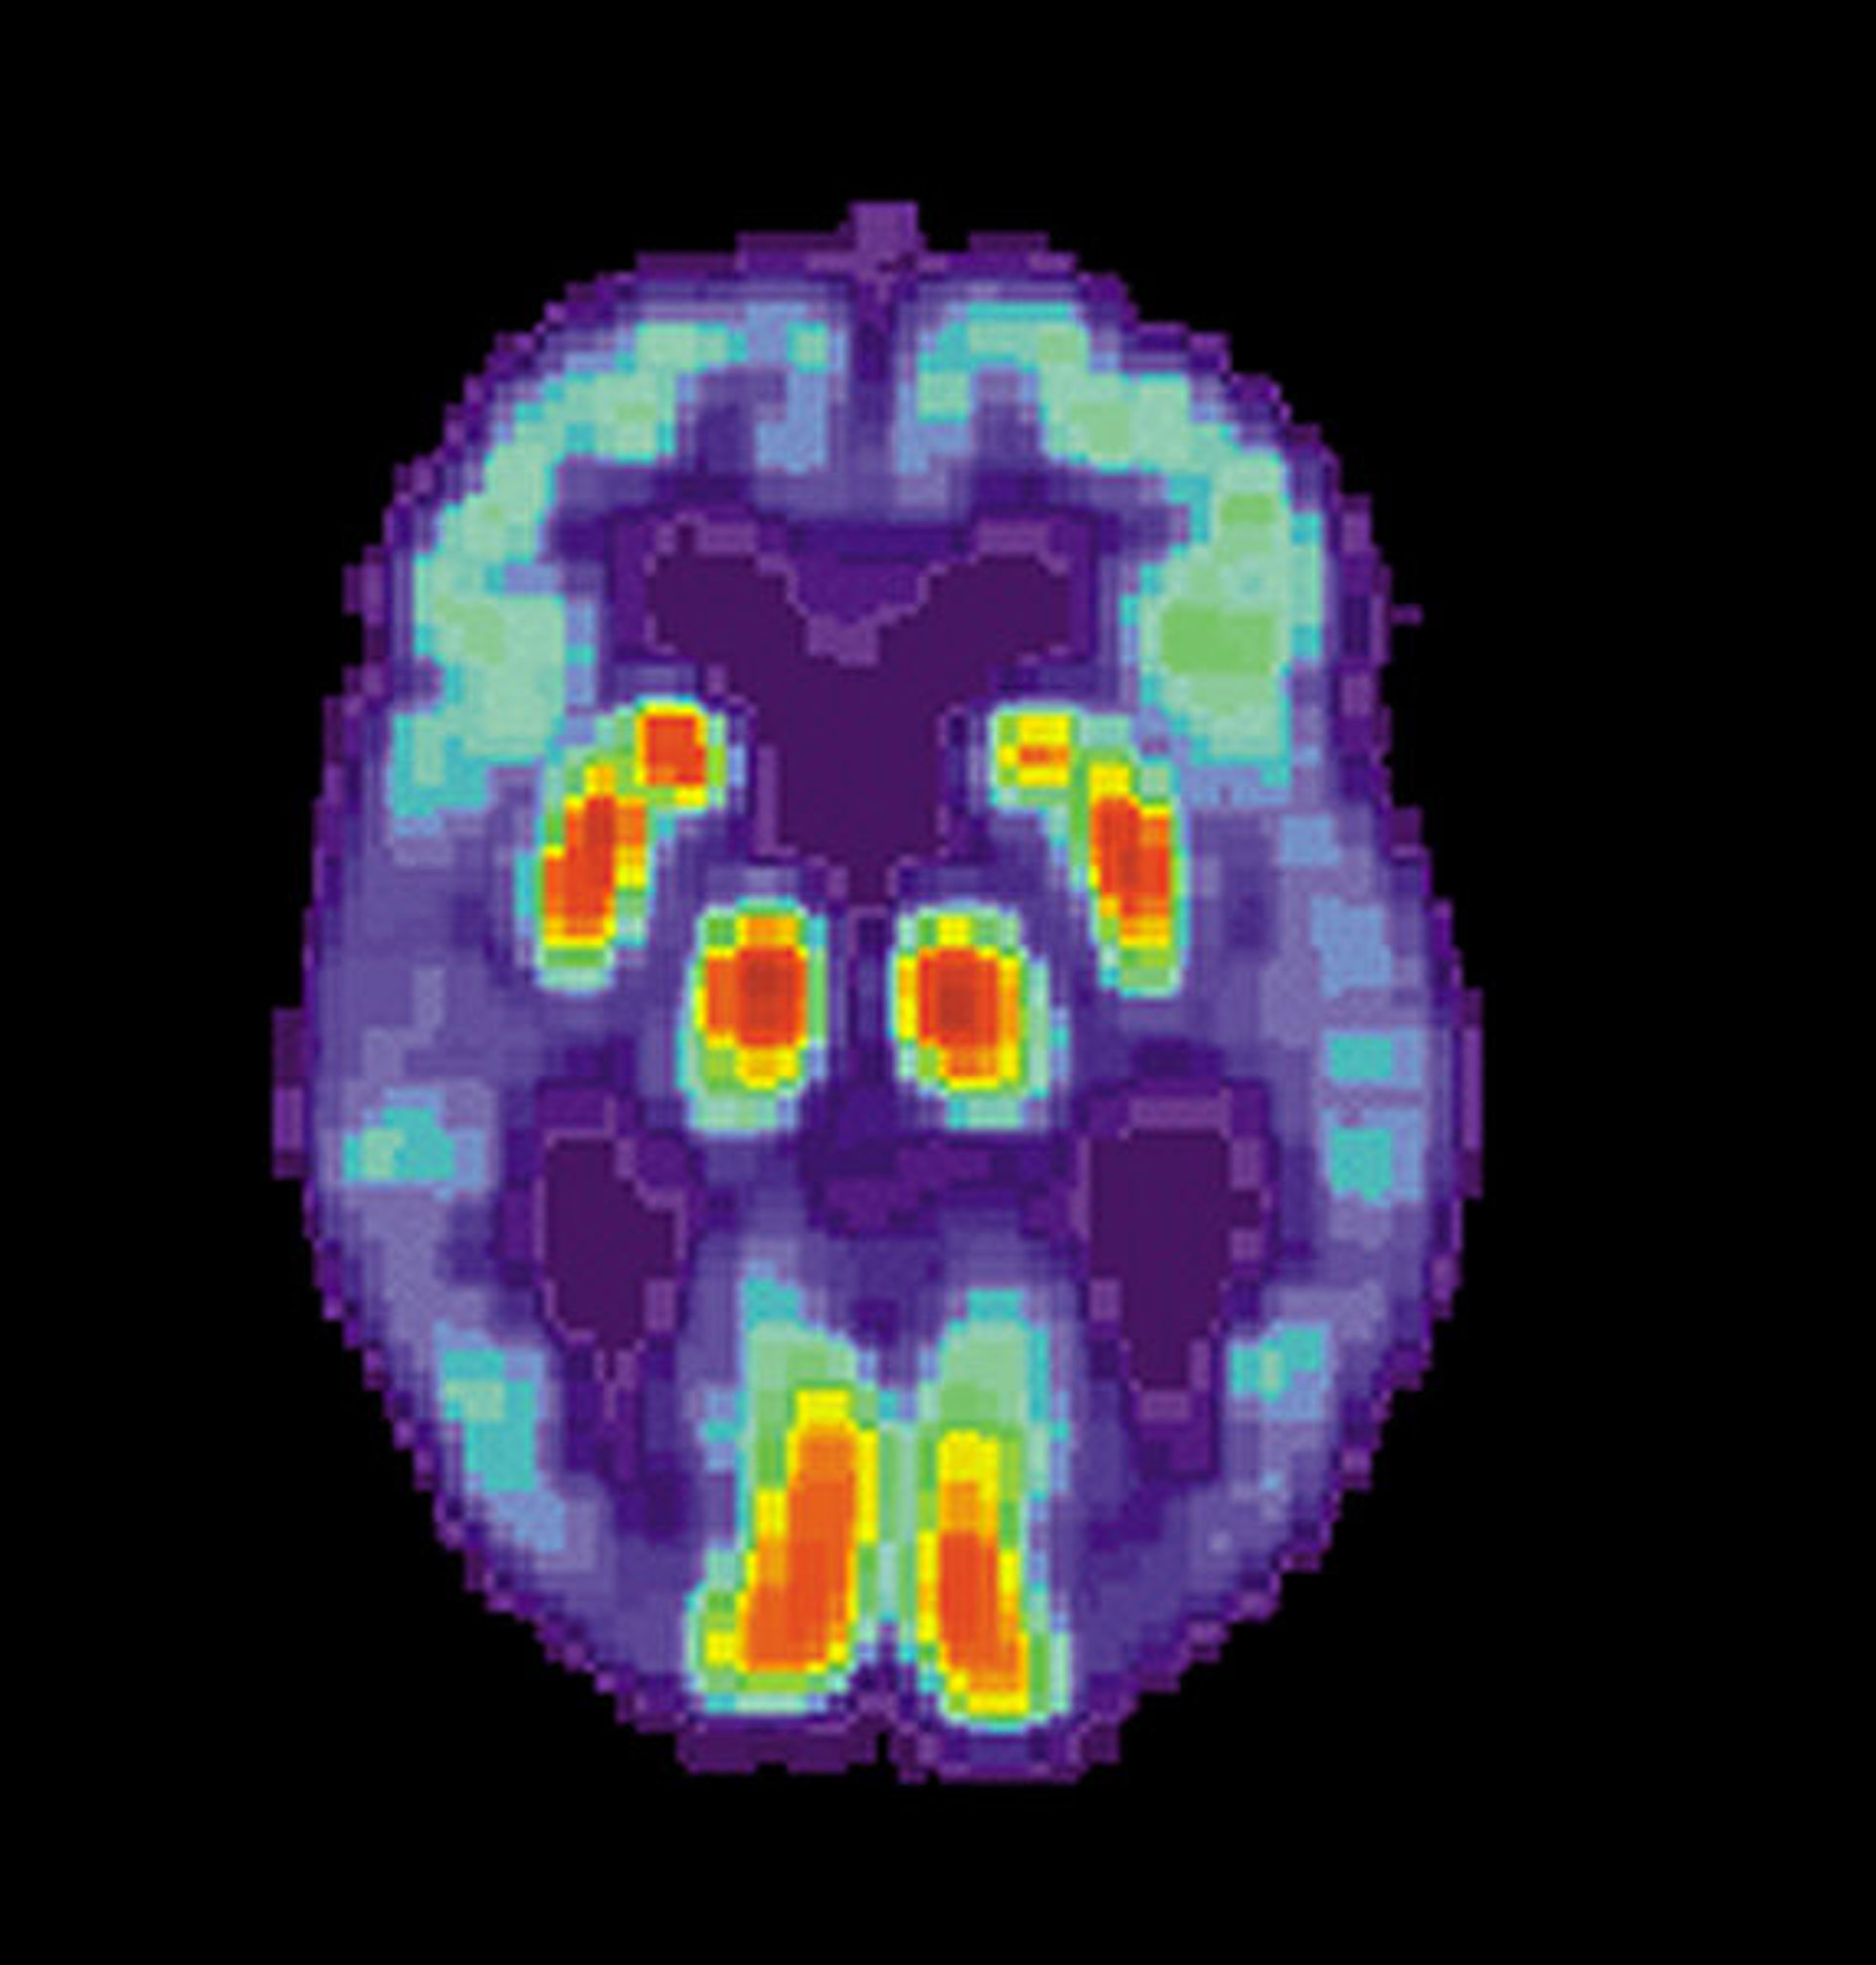

Para poner a punto su sistema, los investigadores procesan imágenes del cerebro adquiridas mediante técnicas de tomografía computerizada, tras la administración de un radiofármaco al paciente por vía intravenosa.

De esta forma, circulan por su organismo sustancias emisoras de radiación que son detectadas por dispositivos que actúan a modo de escáner y, así, los médicos obtienen información de cómo funcionan los órganos. En esta investigación se recogen datos sobre la actividad cerebral, como el flujo sanguíneo o la actividad metabólica. "La utilización de nuevos radiofármacos como el 11C-PIB podría permitir además detectar el depósito de las placas de amiloide que suponen el primer paso de la patología", aclara Ramírez.